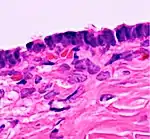

| Functional cyst | Follicular cyst |

|